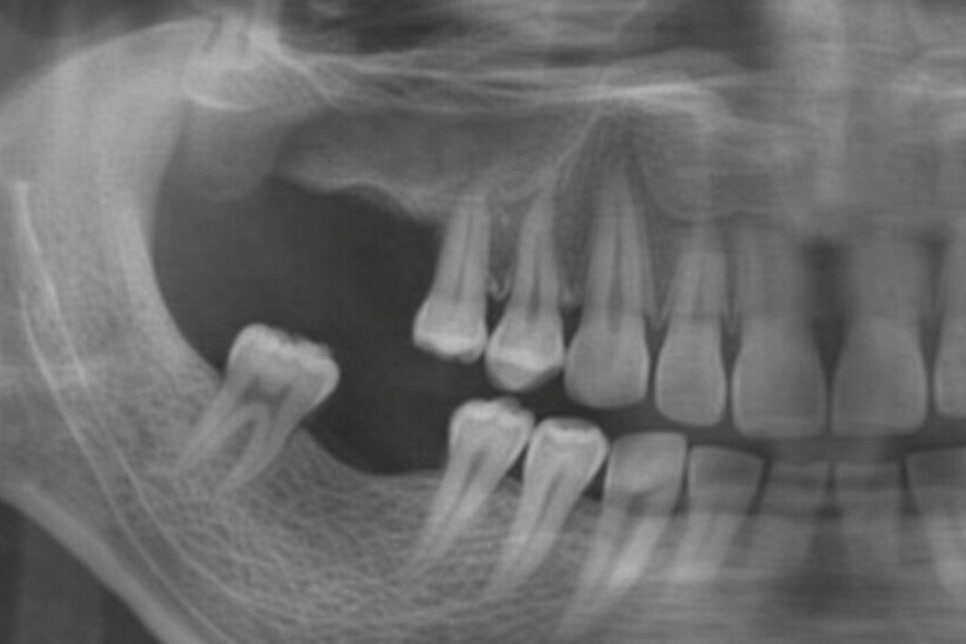

치조골의 상태와 잇몸 조직,

임플란트 식립 위치 등을 종합적으로 분석한 뒤

수술 여부를 판단하는 것이 중요합니다.

다만 모든 환자에게 적용 가능한 방법은 아니며

치조골의 양과 질, 잇몸 조직의 상태,

임플란트 식립 위치 등을 종합적으로 고려해

시행 여부를 판단해야 됩니다.

따라서 정확한 진단을 바탕으로

적합한 치료 방법을 선택하는 것이 중요하죠.

우선 치조골의 양과 밀도가 충분해야 되며

만약 뼈의 양이 부족하다면

대량의 골이식이 필요할 수 있으며

이러한 상황에서는 뼈를 직접 확인하고

처치하기 위해 잇몸 절개가

불가피한 경우가 많습니다.

따라서 flapless 방식은 치조골 상태가

비교적 건강하고 골이식 필요하지 않은 경우에

고려해볼 수 있습니다.